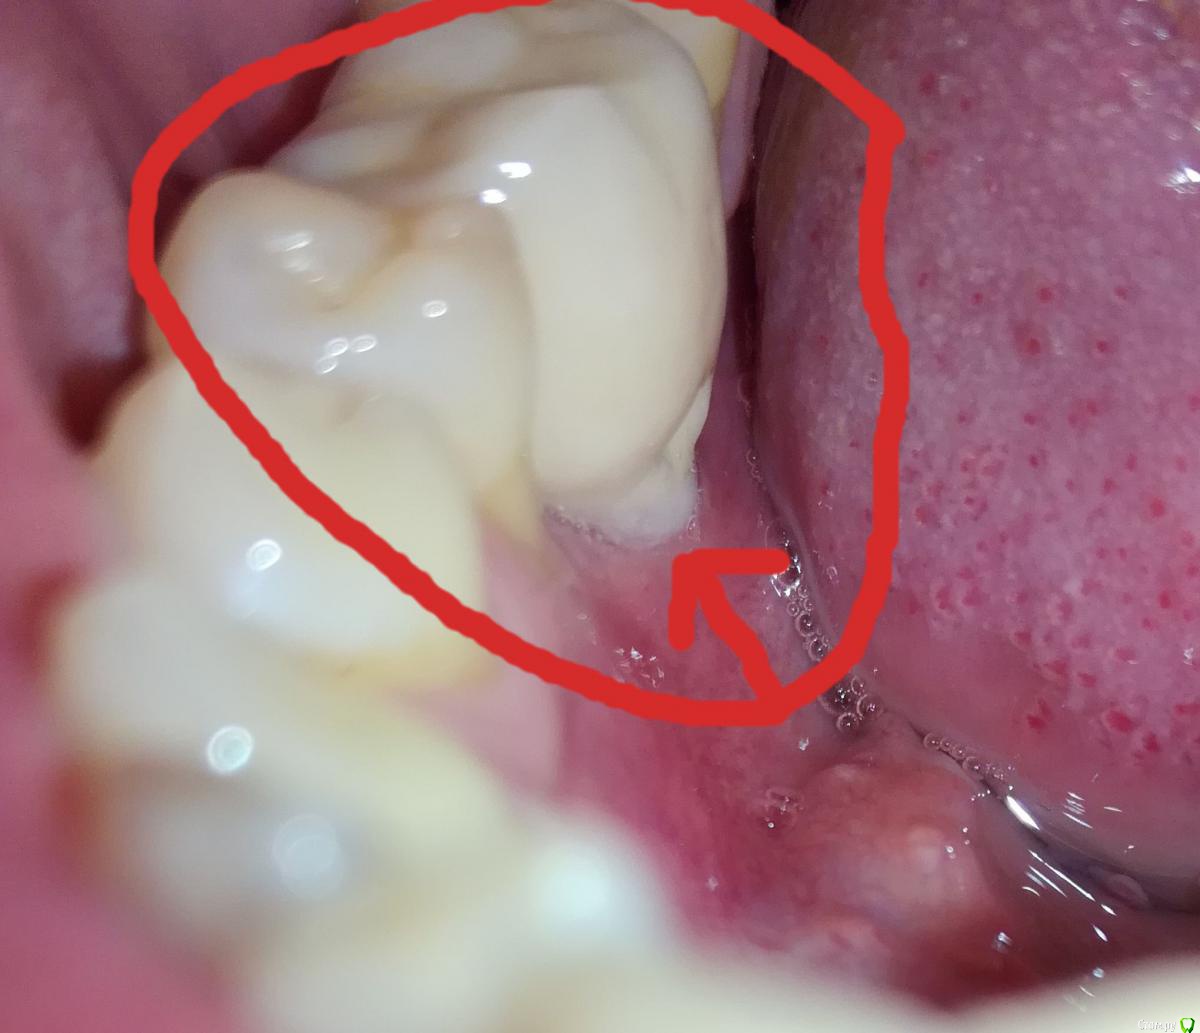

Alex19_73 Опубликовано 3 апреля, 2017 Автор Поделиться Опубликовано 3 апреля, 2017 Первую пластику десны сделали, фото ниже, на днях намечена вторая операция пластики десны.Но обнаружилась проблема в том месте в котором подозревал ее изначально. В четверг начал разглядывать десну со стороны языка и показалось подозрительным что ее край слишком светлый. Разглядел что в районе края десны на коронке какая то неоднородность, ощущение что она трет по десне и похоже десна уже несколько опустилась и вдобавок там не заживающая рана. Фото с кровью было сделано утром до чистки зубов, хотел сделать фотографию, но мешали пузырьки слюны, провел по десне языком и пошла кровь.Врачу еще об этом не говорил. Помогите пожалуйста определиться с тем что делать в такой ситуации, что просить у врача, что должен сделать врач. Коронка несъемная. Ее можно только распилить. Ссылка на комментарий

Alex19_73 Опубликовано 3 апреля, 2017 Автор Поделиться Опубликовано 3 апреля, 2017 здесь наверно лучше видно структуру этого фрагмента , что типа "грозди" Ссылка на комментарий